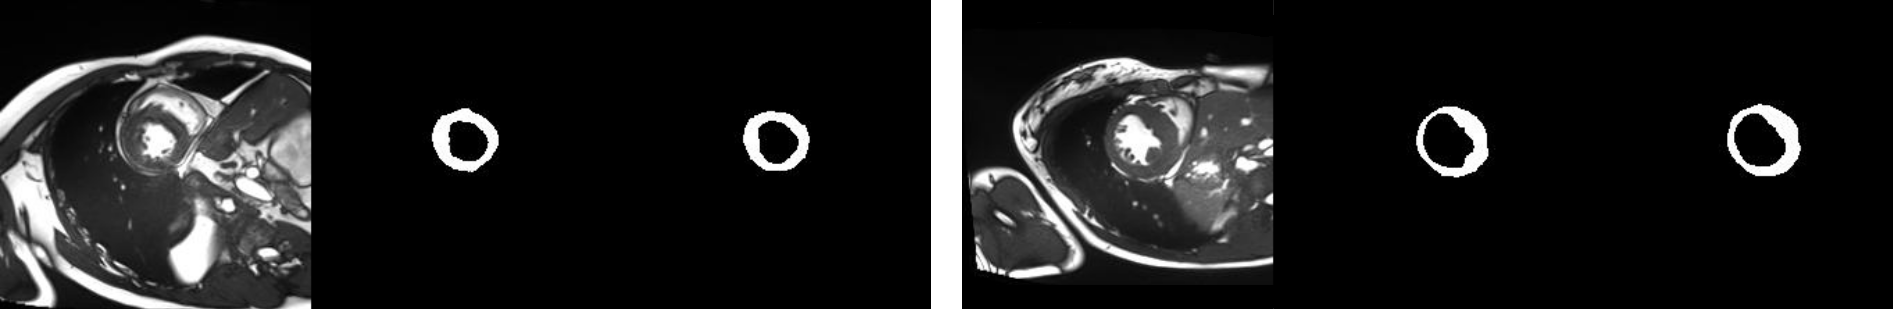

The utility of a factorised representation becomes evident in semi-supervised learning. Qualitatively in Fig. 4 we can see that our method closely follows ground truth segmentation masks (example from ACDC held-out test set).